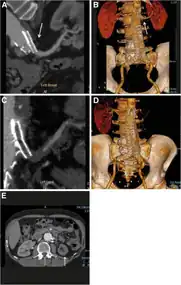

Bilateral renal artery stenosis asterisk (Absent infra-renal aorta arrow)

Bilateral renal artery stenosis asterisk (Absent infra-renal aorta arrow) -

Assessment of kidneys with artery stenosis taken by magnetic resonance angiography

Images a,b,c,d,e) (Malignant) renovascular hypertension caused by a renal artery CG (Chimney graft) occlusion

Images a,b,c,d,e) (Malignant) renovascular hypertension caused by a renal artery CG (Chimney graft) occlusion -